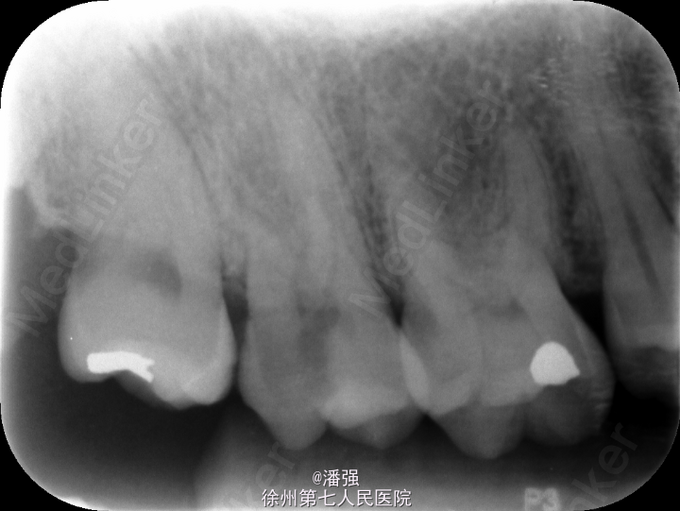

中龋 中龋 慢性牙髓炎

右上后牙冷热刺激痛一周

查体 辅查

17远中深大龋洞,探痛,冷热测激发痛,无叩痛和松动

诊断 处理

17慢性牙髓炎,处理,去腐未尽穿髓,局麻下开髓揭顶,远中腐质去完,平齐牙龈,通根,封药,复诊,根管预备,完成根管充填